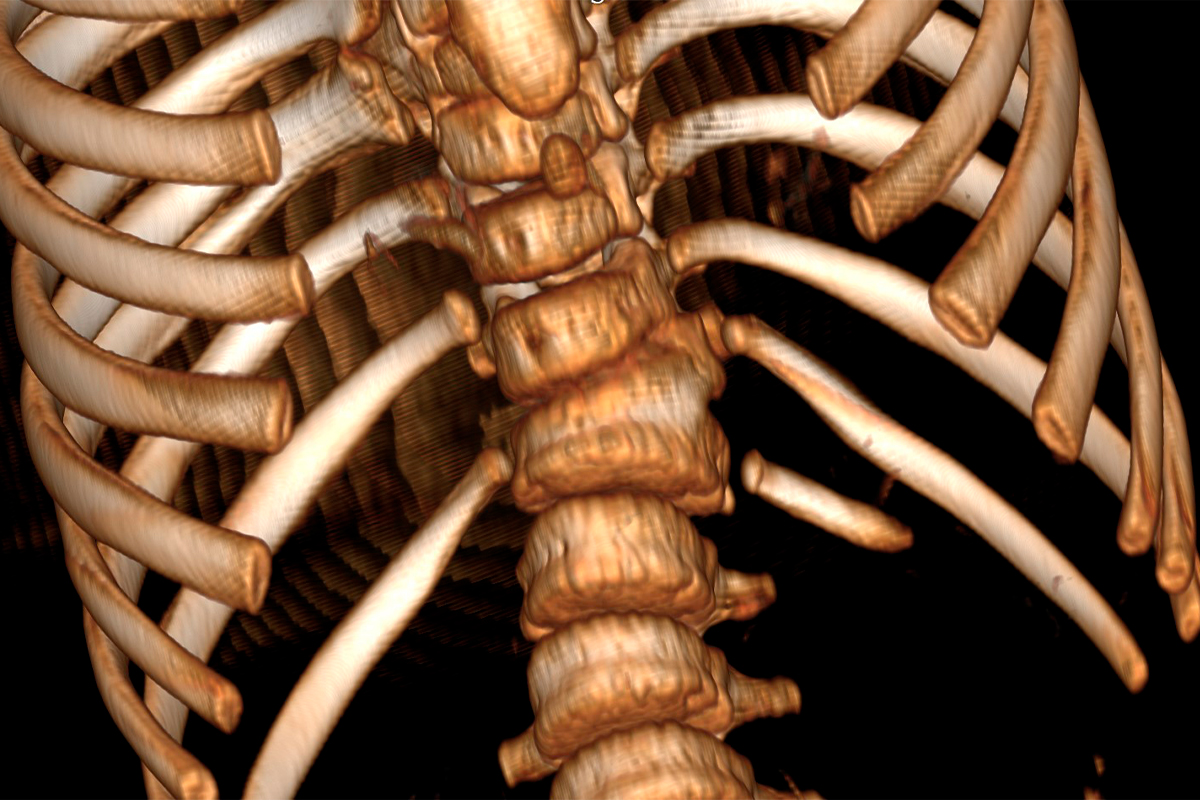

19 февраля совместной белорусско-российской бригадой на базе РНПЦ травматологии и ортопедии была выполнена хирургическая операция ребенку 4 лет с тяжелой врожденной деформацией позвоночника, что стало возможным благодаря реализованной программе Союзного государства «Разработка новых спинальных систем с использованием технологий прототипирования в хирургическом лечении детей с тяжёлыми врождёнными деформациями и повреждениями позвоночника».